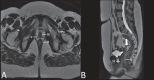

Magnetic resonance imaging is a method with high contrast resolution widely used in the assessment of pelvic gynecological diseases. However, the potential of such method to diagnose vaginal lesions is still underestimated, probably due to the scarce literature approaching the theme, the poor familiarity of radiologists with vaginal diseases, some of them relatively rare, and to the many peculiarities involved in the assessment of the vagina. Thus, the authors illustrate the role of magnetic resonance imaging in the evaluation of vaginal diseases and the main relevant findings to be considered in the clinical decision making process.